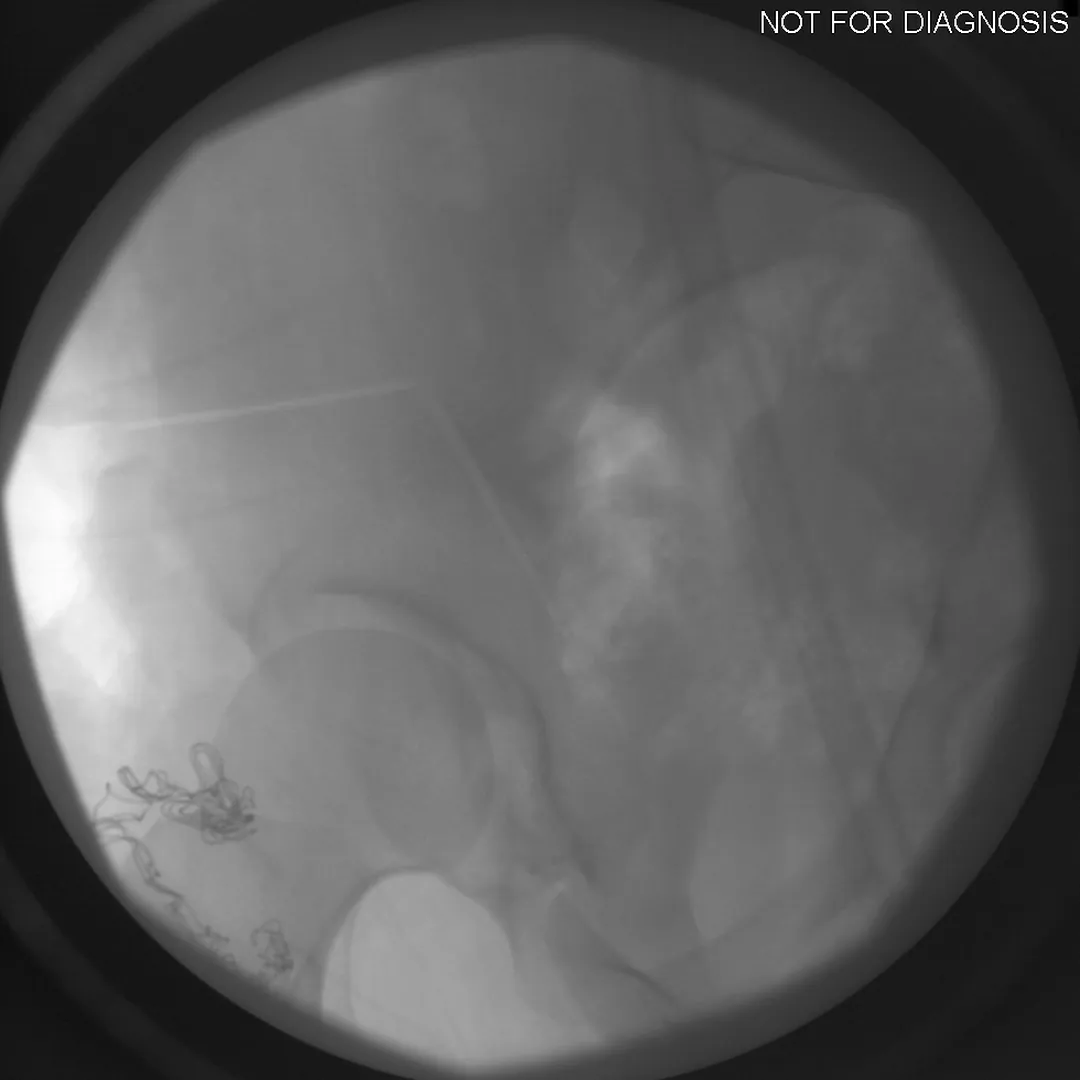

During a PAO, the surgeon carefully cuts the bone around the hip socket and repositions it to provide better coverage of the femoral head. The socket is then fixed in its new position using screws. The goal is to improve hip stability, reduce pain, and preserve the patient’s natural hip joint.

• Several controlled bone cuts are made around the hip socket

• The socket is repositioned and fixed with screws

• The hip joint itself is preserved